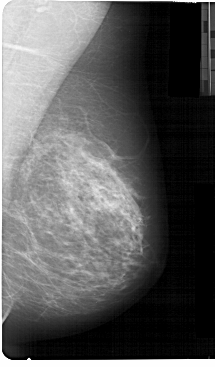

A_1368_1.LEFT_MLO

LEFT_MLO LINES 5491 PIXELS_PER_LINE 3496 BITS_PER_PIXEL 12 RESOLUTION 43.5 OVERLAY